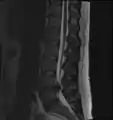

L'imagerie par résonance magnétique peut montrer la hernie, le canal vertébral, les nerfs, les tissus environnants. Les tissus mous sont les mieux analysés par cet examen qui est le plus performant pour le diagnostic de hernie discale. Les images pondérées en T2 montrent clairement la hernie.

IRM lombosacrée sagittale montrant une hernie discale de niveau L4-L5.

IRM lombaire sagittale montrant une hernie discale de niveau L4-L5.

IRM lombaire sagittale montrant des protrusions discales.